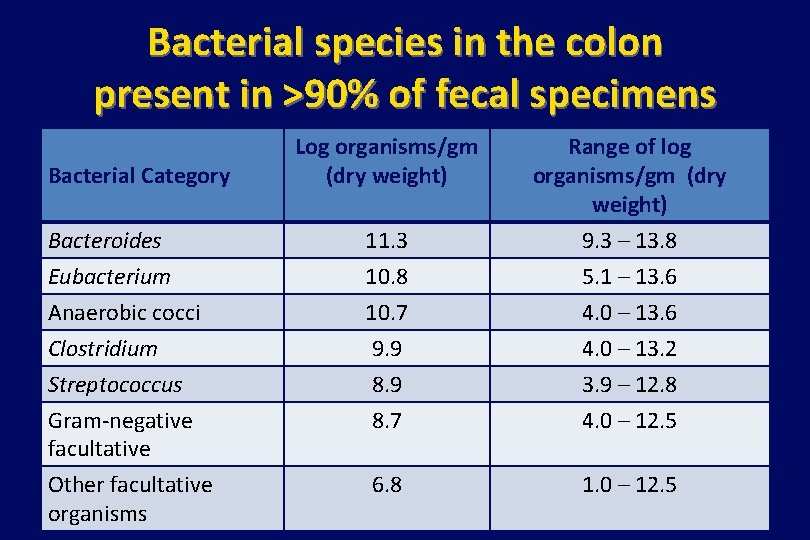

Bacterial species in the colon present in >90% of fecal specimens Bacteroides 11. 3 Range of log organisms/gm (dry weight) 9. 3 – 13. 8 Eubacterium Anaerobic cocci Clostridium Streptococcus Gram-negative facultative Other facultative organisms 10. 8 10. 7 9. 9 8. 7 5. 1 – 13. 6 4. 0 – 13. 2 3. 9 – 12. 8 4. 0 – 12. 5 6. 8 1. 0 – 12. 5 Bacterial Category Log organisms/gm (dry weight) Data Source: Mandell et al. Principles & Practice of infectious Diseases